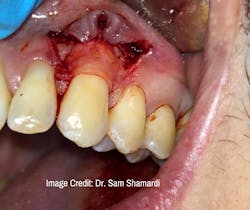

Dr. Sam Shamardi: Connective tissue grafting is a gold-standard technique for root coverage. Harvesting tissue from a donor site provides ideal tissue match, and studies show long-term stability to be superior to alternative methods such as membranes or alloderm. The donor site tissue completely regenerates and could have a new graft harvested after six weeks of healing.

Dr. Sam Shamardi: Part of the benefit of using connective tissue opposed to alternative materials is that the graft does not need to be fully covered in order to heal; partial exposure can still result in excellent results as long as the majority (at least 2/3) of the graft is covered and receives blood supply. This provides further flexibility in comparison to alloderm, where even a slight amount of exposure at any point could result in failure.